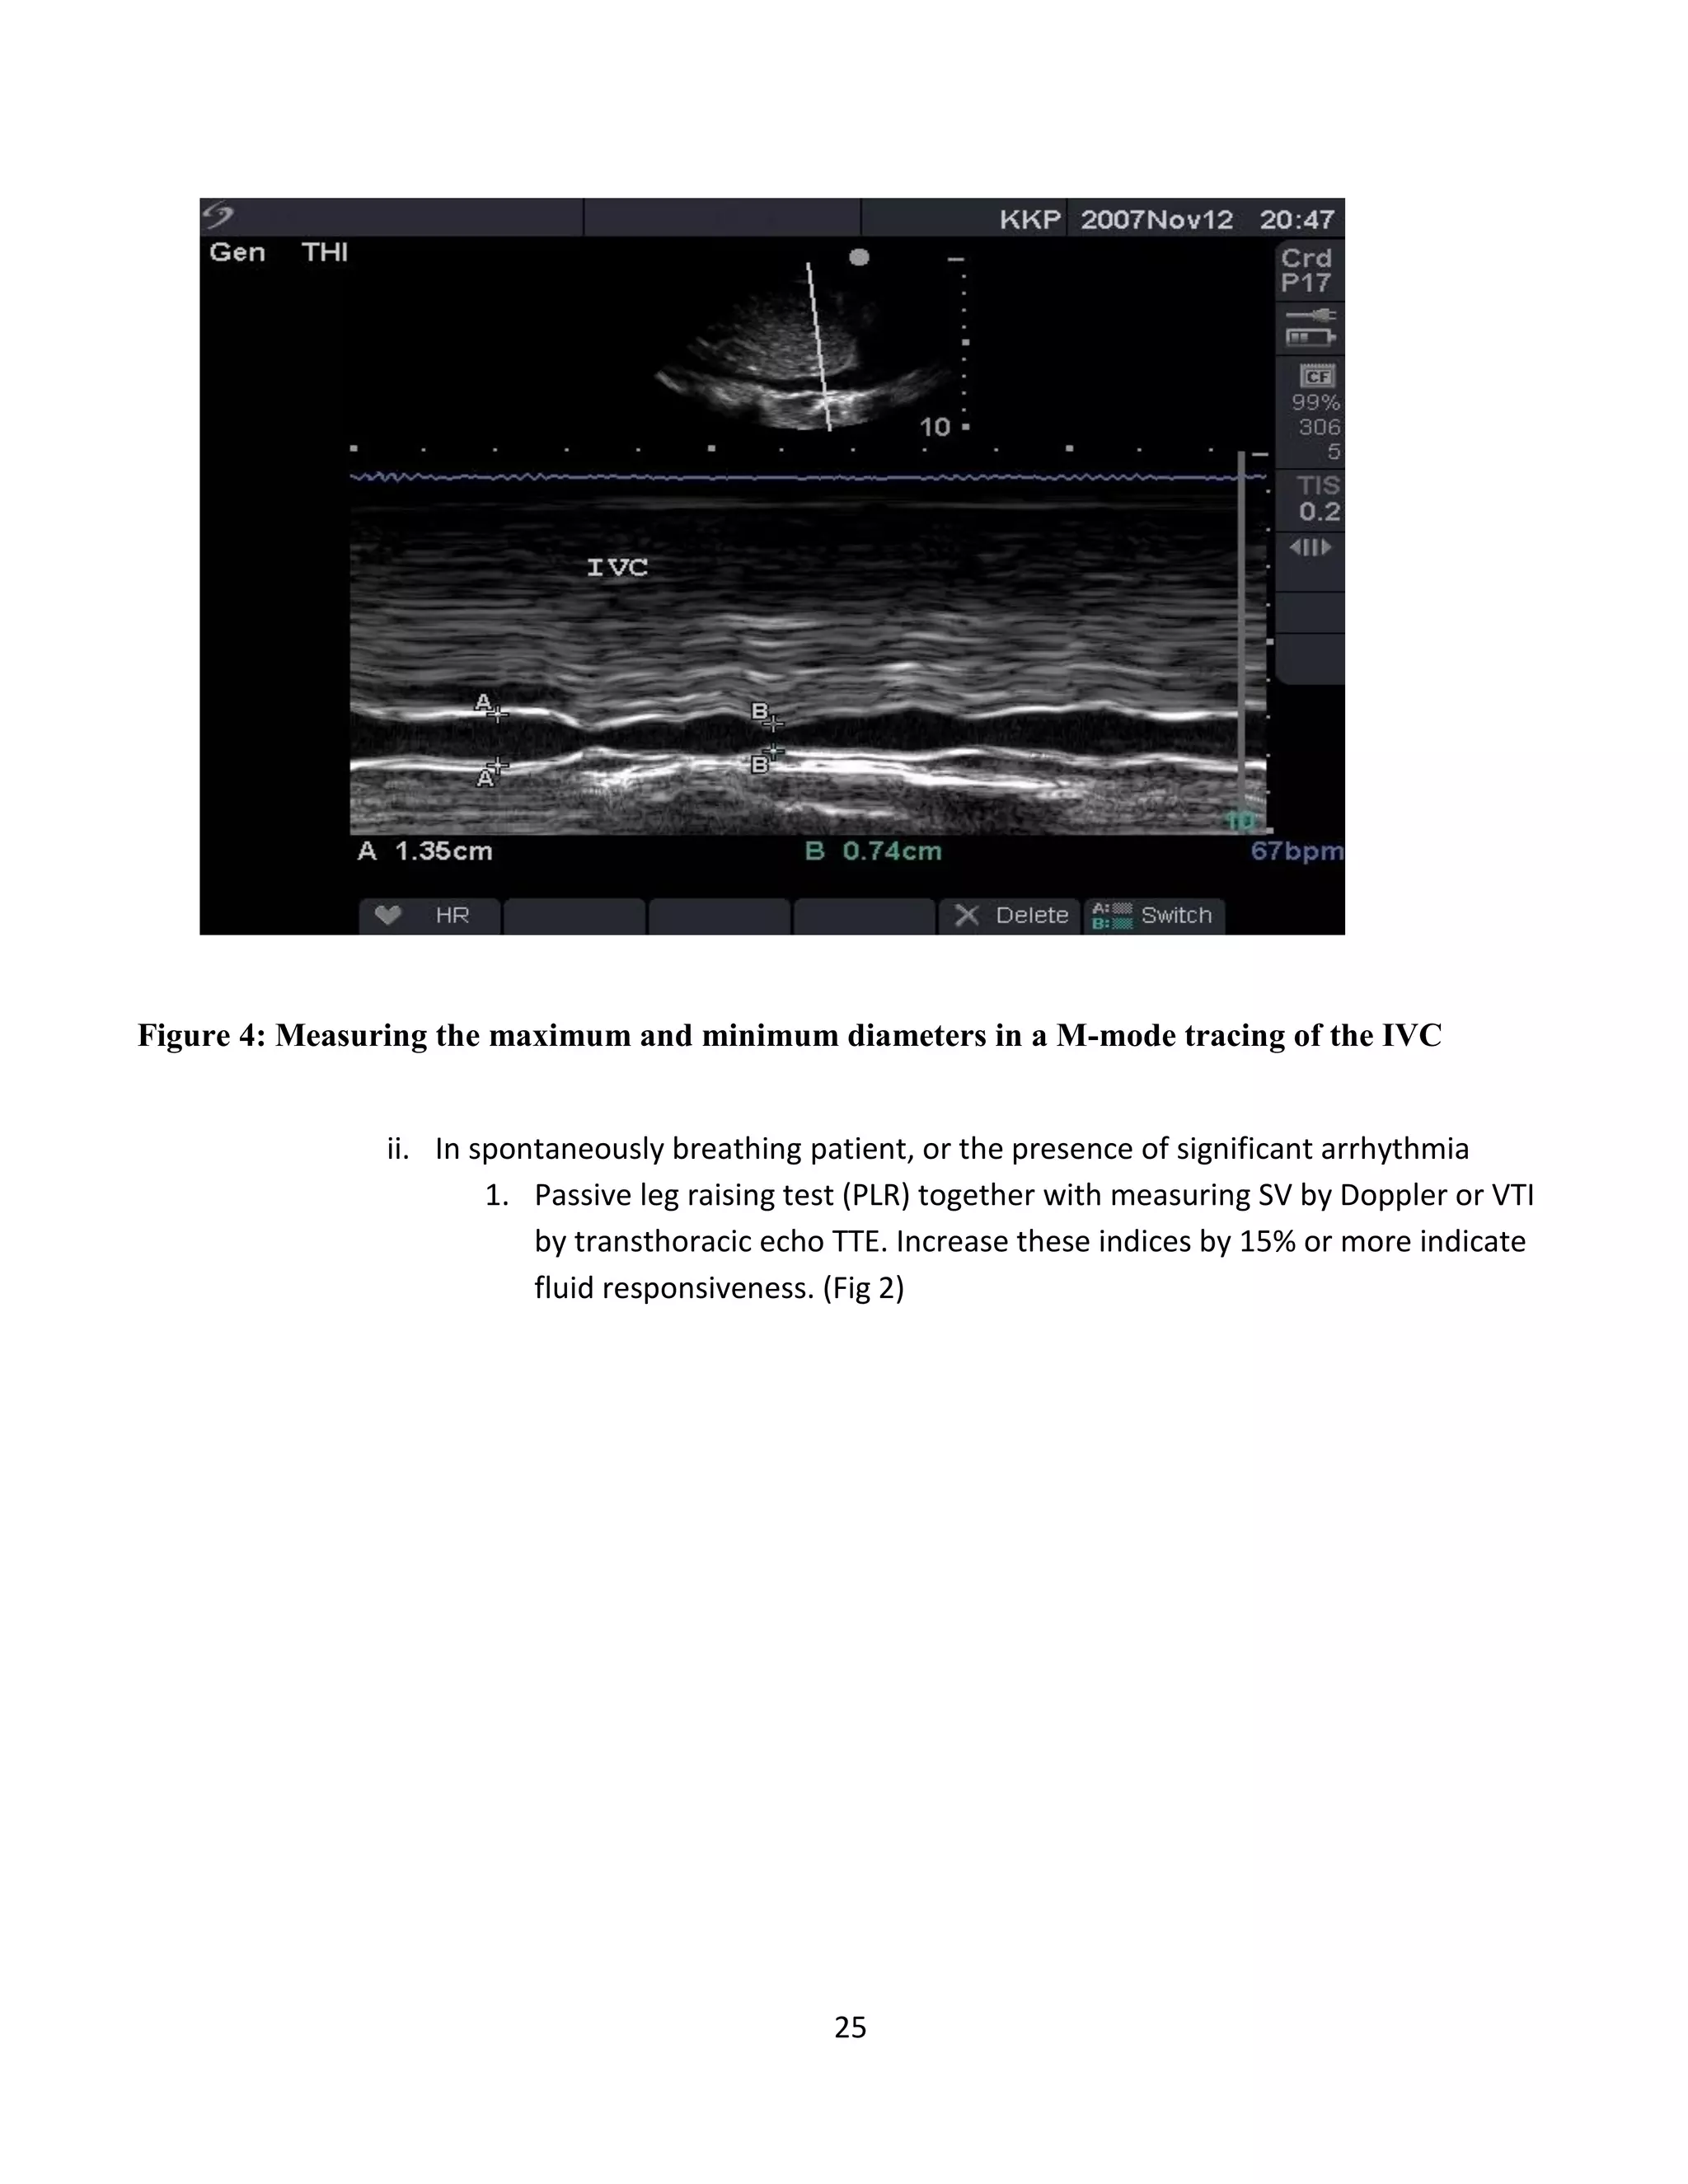

Figure 4: Measuring the maximum and minimum diameters in a M-mode tracing of the IVC

ii. In spontaneously breathing patient, or the presence of significant arrhythmia

1. Passive leg raising test (PLR) together with measuring SV by Doppler or VTI

by transthoracic echo TTE. Increase these indices by 15% or more indicate

fluid responsiveness. (Fig 2)